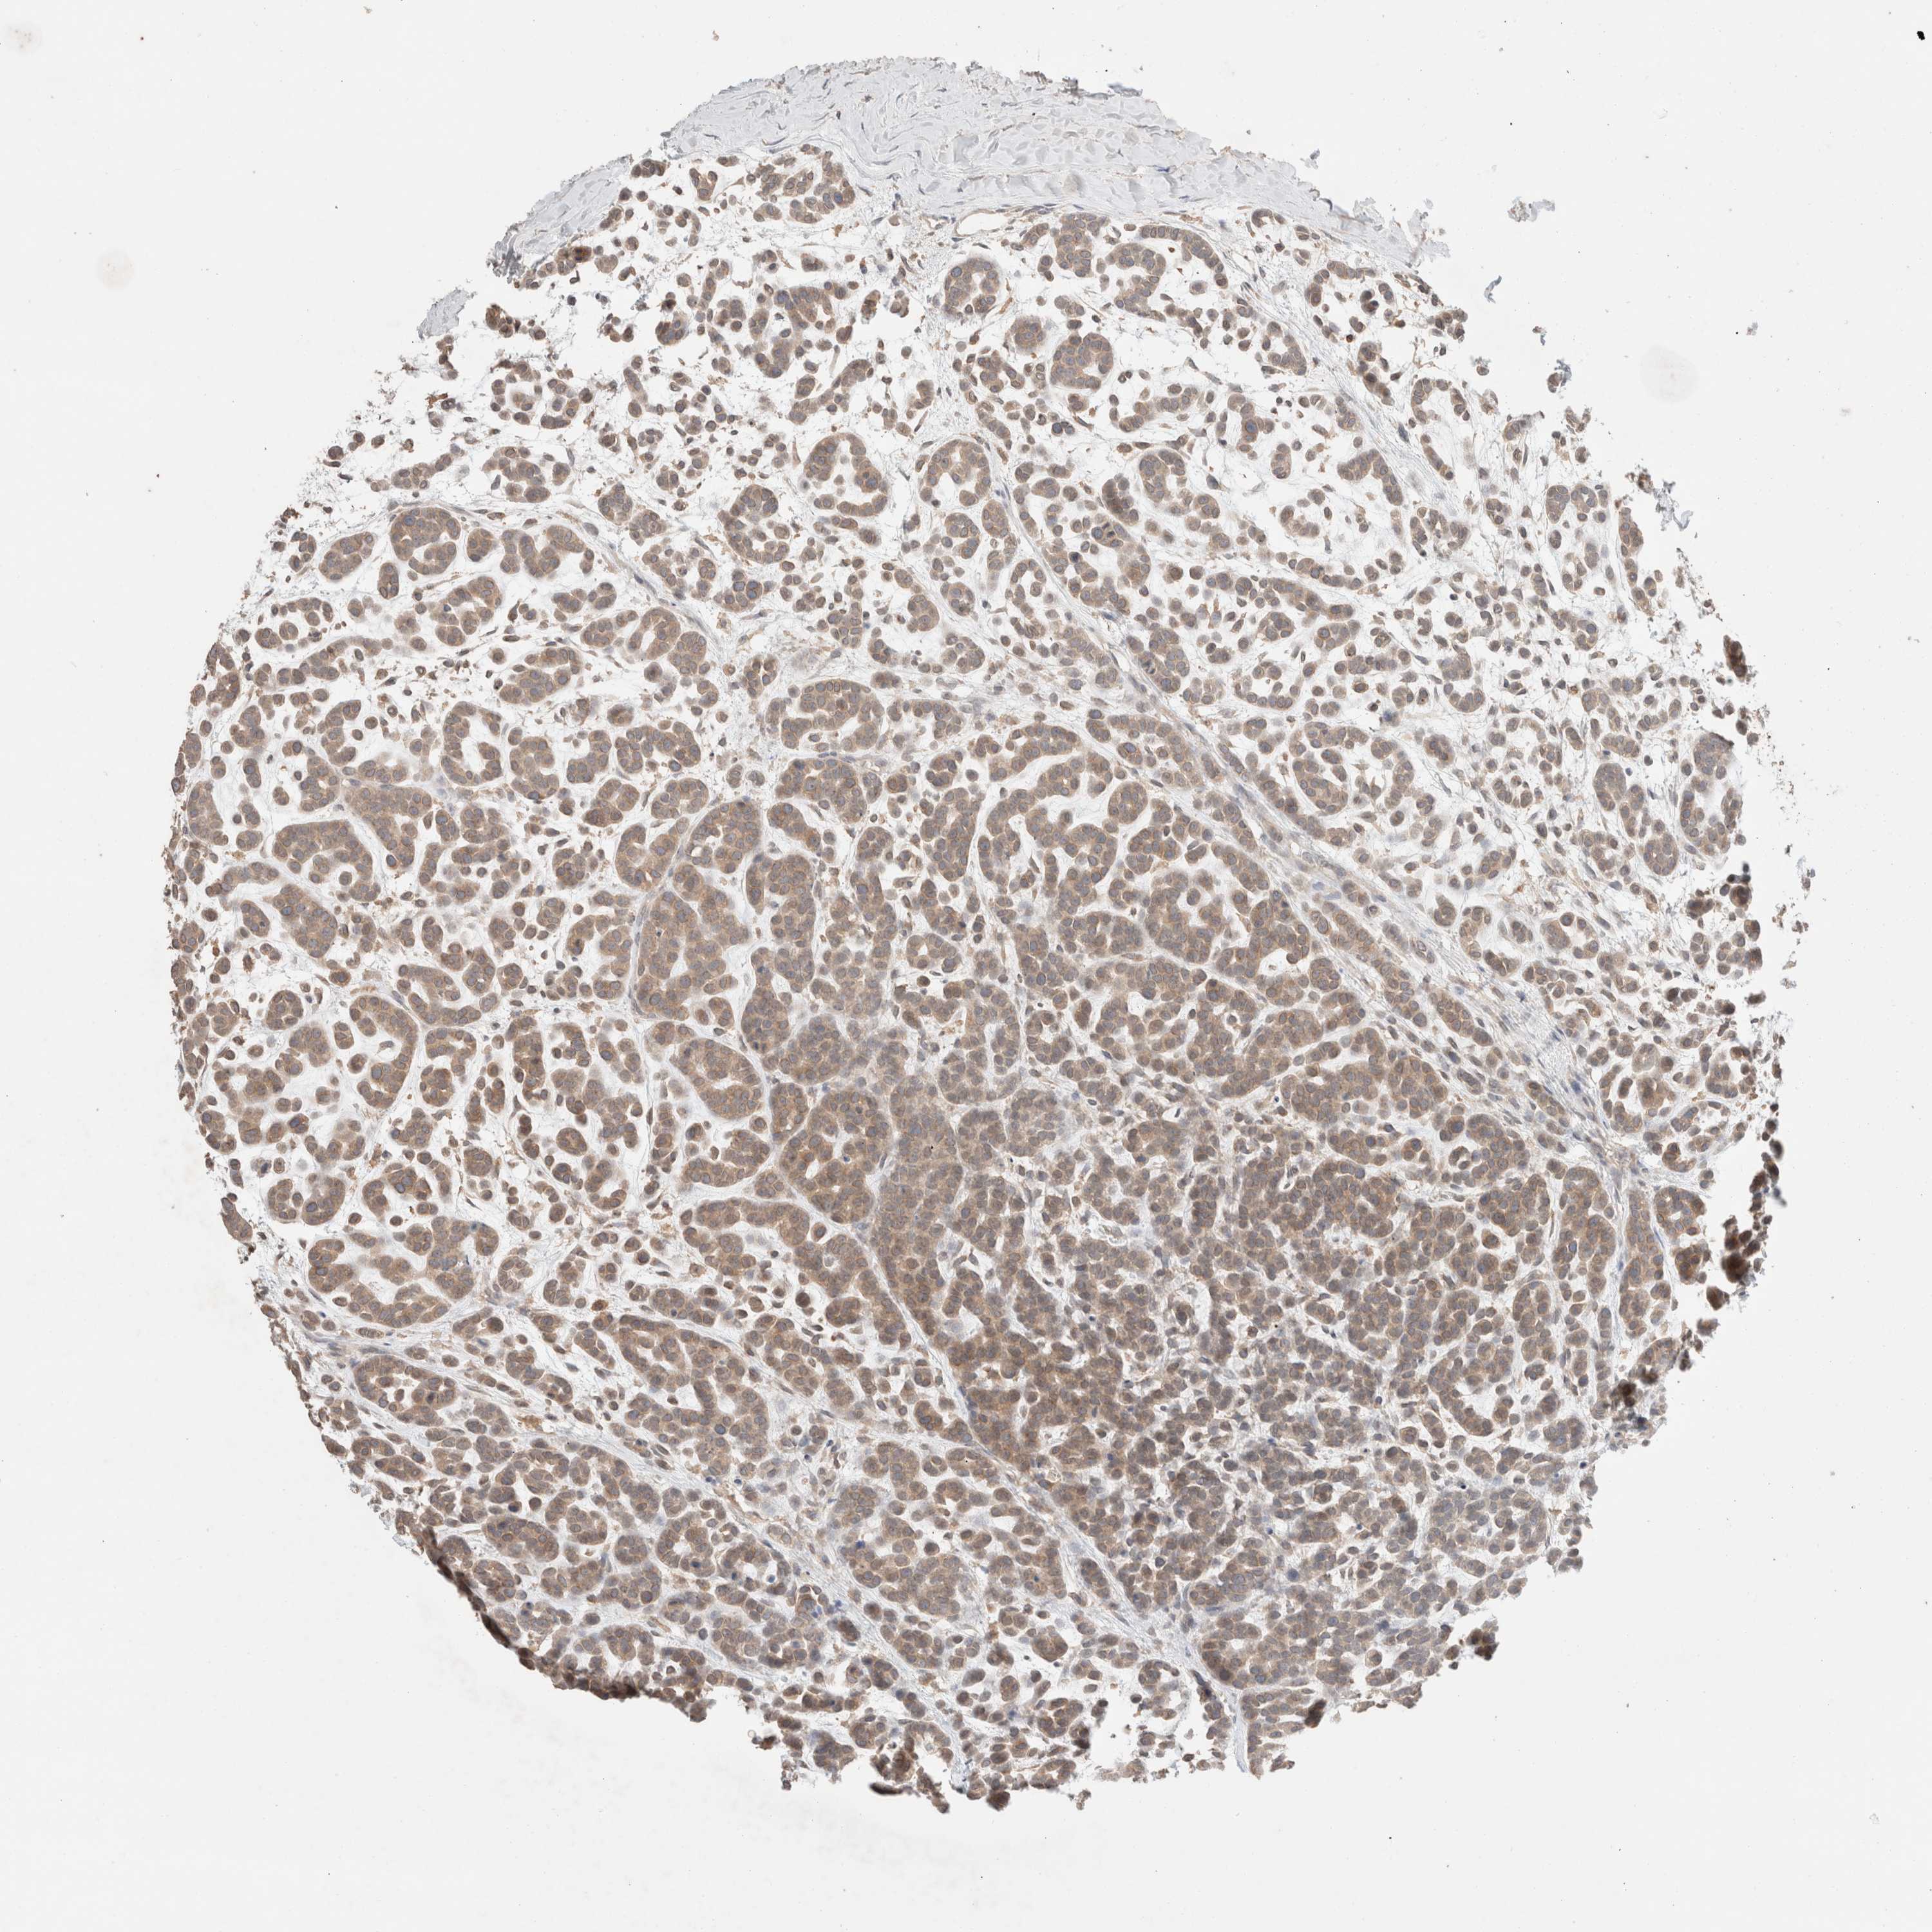

HEAD AND NECK CANCER - Protein expressioni

A mouse-over function shows sample information and annotation data. Click on an image to view it in a full screen mode. Samples can be filtered based on level of antibody staining by selecting one or several of the following categories: high, medium, low and not detected. The assay and annotation is described here.

Antibody stainingi

Antibody staining in the annotated cell types in the current human tissue is reported as not detected, low, medium, or high, based on conventional immunohistochemistry profiling in selected tissues. This score is based on the combination of the staining intensity and fraction of stained cells.

Each image is clickable and will lead to virtual microscopy that enables deeper exploration of all samples and also displays staining intensity scores, fraction scores and subcellular localization as well as patient and tissue information for each sample.

Antibody HPA024204

Staining

High

Medium

Low

Not detected

Intensity

Strong

Moderate

Weak

Negative

Quantity

>75%

75%-25%

<25%

None

Location

Nuclear

Cytoplasmic/membranous

Cytoplasmic/membranous,nuclear

Squamous cell carcinoma, NOS